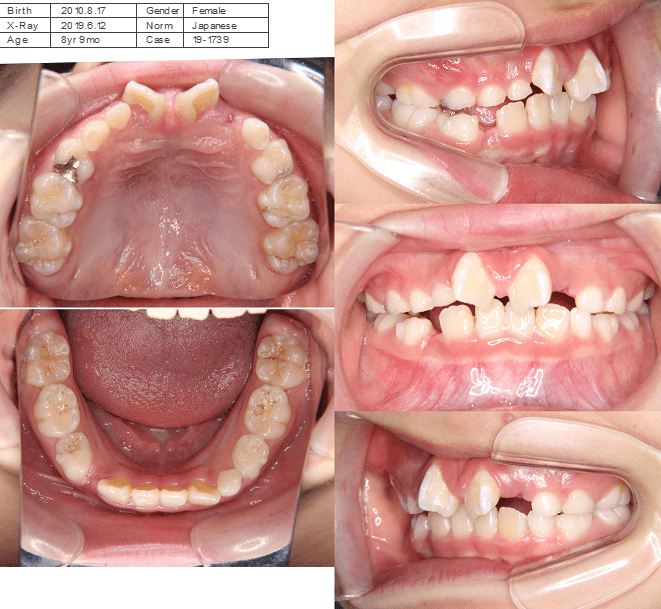

| 年齢・性別 | 8歳9ヶ月の女児 |

|---|---|

| 主訴 | 歯並びの乱れを気にされて来院された患者様です。将来的なスペース不足と歯のねじれ(翼状捻転)が懸念されました。 |

| 治療期間・回数 | 2年10ヶ月・19回 |

| 費用 | 430,000円(税別) |